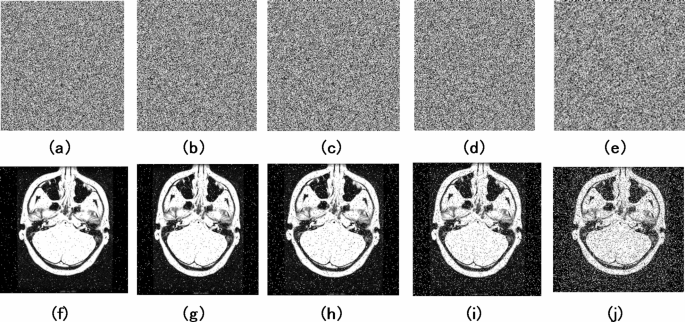

Noise attack analysis

To test the algorithm’s efficacy against noise attacks, the cipher image is subjected to salt and pepper noise of various intensity levels. Salt and pepper noise is applied to the cipher image with varying intensity levels, such as 2%, 3%, 5%, 10% and 25%. The corresponding deciphered images are analysed, as shown in Fig. 12. The PSNR values of the original and the deciphered images from the noise-affected cipher images are calculated and tabulated in Table 11. This shows the robustness of the encryption algorithm against noise attacks.

Salt and pepper noise attack analysis: (a) Encrypted image with 2% noise, (b) Encrypted image with 3% noise, (c) Encrypted image with 5% noise, (d) Encrypted Image with 10% noise, (e) Encrypted Image with 25% noise, (f) Deciphered Image of (a), (g) Deciphered Image of (b), (h) Deciphered image of (c), (i) Deciphered image of (d), (j) Deciphered image of (e).